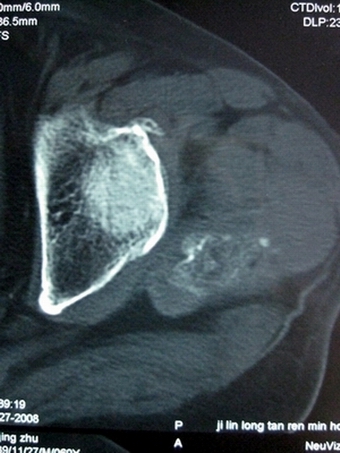

以下是引用lkc8963在2008-12-19 21:19:00的发言:[br]左?右?患侧大转子上移,股骨颈骨质浓杂,髋周见多发条片状骨化影,以小转子为著,多为陈旧性股骨颈骨折后改变并骨化性肌炎.请咨询既往史!